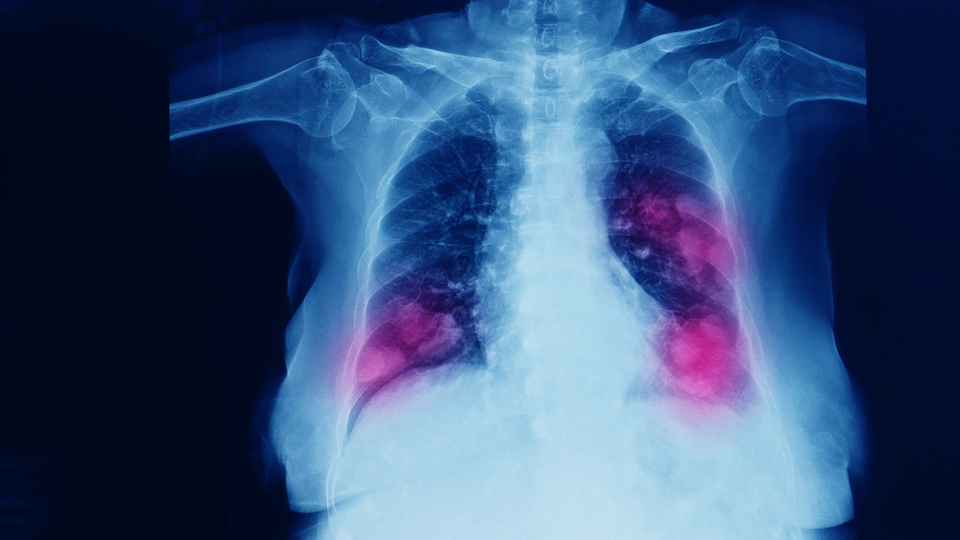

Prof. Dr. Cihan, “Baktığımızda erkeklerde en çok görülen kanser tipi akciğer kanseri ve akciğer kanserinin de yüzde 90 ila 95 sebebi ne yazık ki tütün kullanımı, sigara kullanımı. Ülkemizdeki 2019 yılı verilerine göre her 2 kişiden 1'i sigara içiyor. 3'te 1 kişi ise her gün tüketiyor sigarayı ve daha seyrek içebilse de ne yazık ki vatandaşlarımızın 3'te 1'i her gün sigara kullanmakta. 35 ila 44 yaş erkek grubuna baktığımızda 3 erkekten 2'sinin gene sigara kullandığını, kadın grubunda ise 4 kadından 1'inin sigara içtiğini görüyoruz. Ne yazık ki oranlar ülkemizde sigara tüketimi açısından oldukça yüksek. Akciğerde kanser yapmasının yanı sıra sigara aynı zamanda gırtlak kanseri, ağız boşluğundaki kanserler, dudaktaki kanserler, yutakta, yemek borusunda, midede, kalın bağırsakta, pankreas, böbrek, mesane, meme ve rahim ağzı kanserlerinde de önemli rol oynuyor etken olarak. İnsanlardaki bütün kanserlerin yaklaşık üçte birinden sigara sorumludur” şeklinde konuştu.